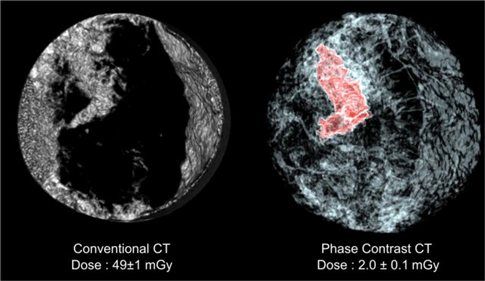

Τώρα, ερευνητές από τις ΗΠΑ και τη Γερμανία αναφέρουν ότι ανέπτυξαν μια νέα τεχνική που επιτρέπει την απεικόνιση του μαστού σε τρεις διαστάσεις με την ανάλυση που προσφέρει η αξονική τομογραφία. Η δόση ακτινοβολίας, όμως, είναι 25 φορές μικρότερη.

Η νέα μέθοδος βασίζεται σε δύο καινοτομίες. Η πρώτη αφορά τους αλγόριθμους επεξεργασίας των δεδομένων, η οποία επιτρέπει στην τεχνική να δημιουργεί τρισδιάστατες απεικονίσεις συνδυάζοντας έναν μικρό αριθμό εικόνων που έχουν ληφθεί από διαφορετικές γωνίες.

Η δεύτερη καινοτομία αφορά την πηγή των ακτίνων Χ. Οι ερευνητές χρησιμοποίησαν μια δέσμη ακτίνων Χ υψηλής ενέργειας την οποία παράγει η Ευρωπαϊκή Εγκατάσταση Ακτινοβολίας Σύγχροτρου στη Γκρενόμπλ της Γαλλίας (ESRF).

Το ενδιαφέρον είναι ότι, παρόλο που η δέσμη έχει υψηλότερη ενέργεια από ό,τι οι ακτίνες Χ στην ακτινογραφία και την αξονική τομογραφία, οι ιστοί εμφανίζονται πιο διαφανείς στις ακτίνες υψηλής ενέργειας και η απορρόφηση ακτινοβολίας μειώνεται έτσι σημαντικά.